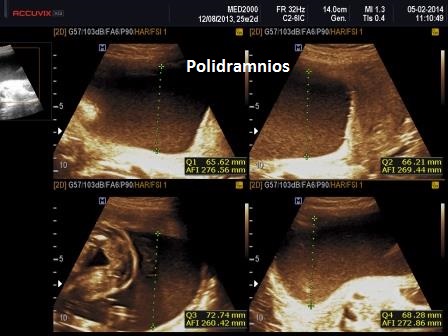

3. polidramnios